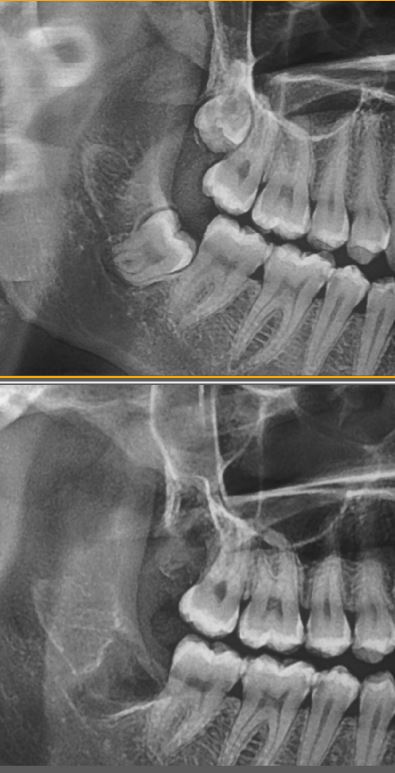

Çıkmaya çalışan göbek 20 yaş dişleri çene kemiklerinde ağrıya neden olabilir. Bütün dişlerim ağrıdığı hissi 20 yaş dişlerinin baskısı nedeniyle de kaynaklanıyor olabilir. Gerçek durumun ne olduğunu anlamak için bir film çekilip bakılması gerekecektir. Çekilen film de 20 yaş dişlerinin pozisyonları ve ağızdaki diğer dişleri çürük olup olmadığı görülür.